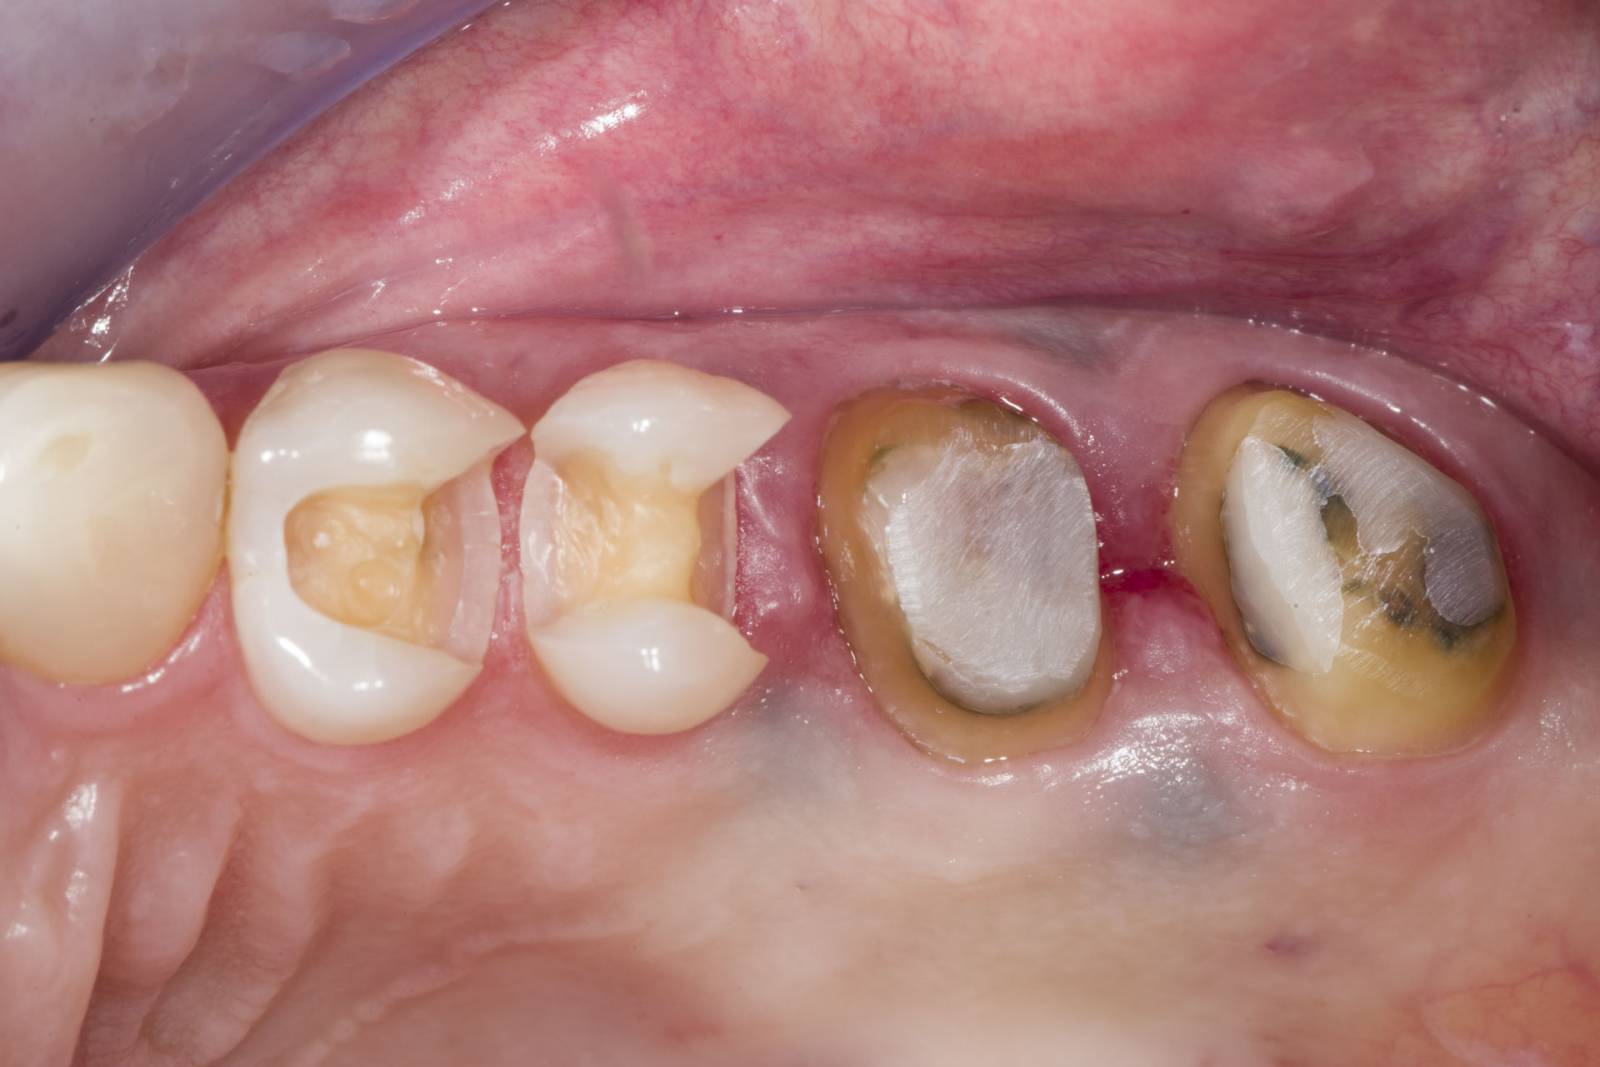

Before

A large carious mesial lesion on tooth 15. The tooth showed asymptomatic apical periodontitis and a significant loss of tooth structure.

After

Chairside-fabricated restoration made of CEREC MTL Zirconia designed using the Biogeneric individual function in the CEREC Software.